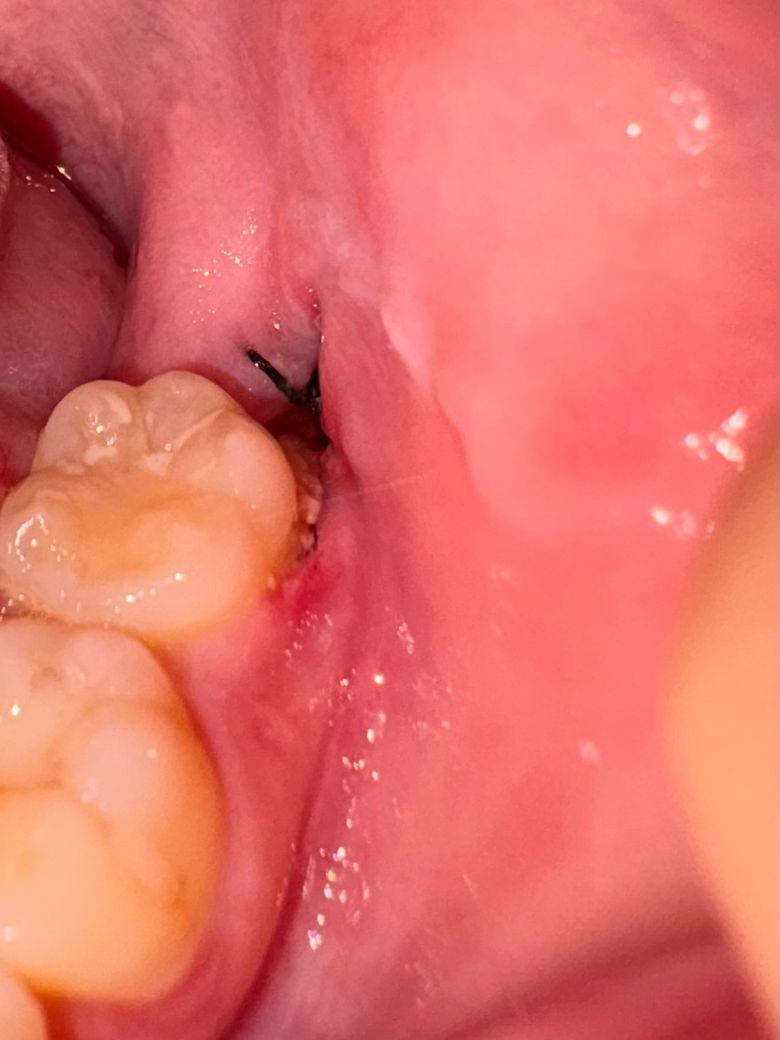

매복 사랑니 발치 부위 하얀 찌꺼기 생김

사진처럼 이빨 뽑은 언쪽이랑 그 앞에 이빨쪽에 하얀 찌꺼기 같은게 생겼어요. 가끔 입에 돌아다녀서 뱉기도 하는데 원래 이런건가요? 아프진 않은데 염증인가요?

뽑은지 일주일 정도 됐는데 잇몸도 부어있어요. 이것고 괜찮은건가요 ㅠ?

• 2번 째 사진

염증은 아니고 사랑니발치한곳 잇몸이 아물면서 생기는 자연스러운 현상이니 크게 걱정하지 않으셔도 될것같습니다.

사진상 보여지는 잇몸 붓기 정도는 발치 후 정상 범주로 보여집니다.

하얀찌꺼기는 이물질 같으니 그냥 뱉으시고, 위생관리 잘해주시기 바랍니다.